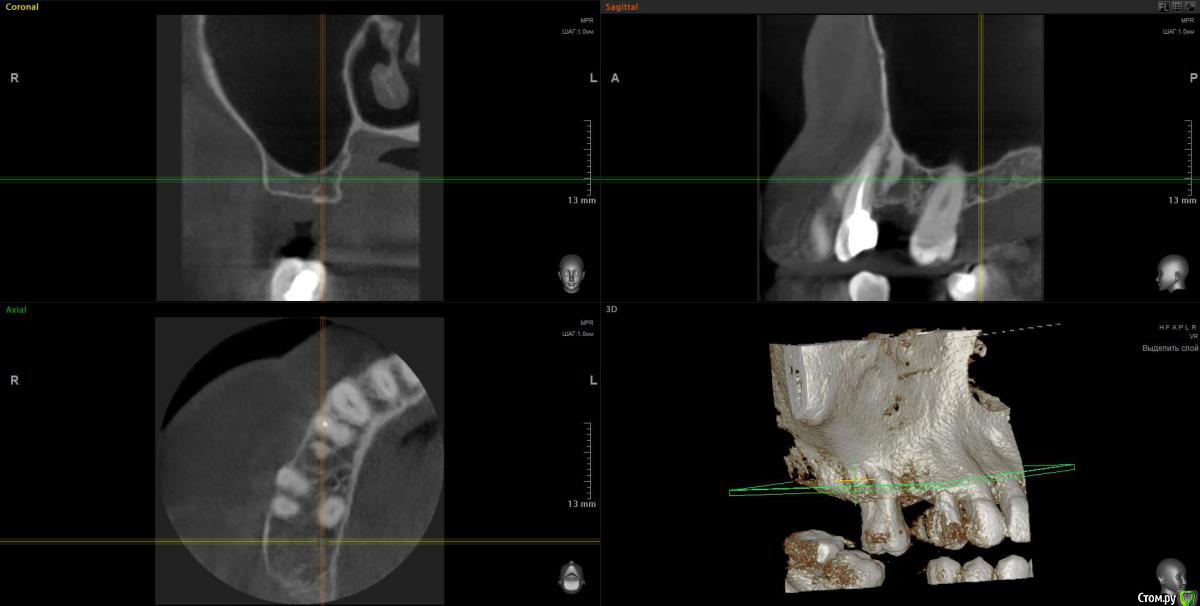

Elena64 Опубликовано 10 мая, 2018 Поделиться Опубликовано 10 мая, 2018 Добрый день!Удалили зуб пятерку справа10 месяцев назад,по словам хирурга,от зуба практически ничего не осталось,он был очень хрупкий.Долго не зарастала лунка,несколько раз обращалась к врачу,кот.удалял,но он проблемы не видел,вроде как заживает нормально,пришлось пропить аб через 1.5 месяца после удаления,т.к. предстояла поездка ,которую нельзя было отменить.На фоне приема аб цефтриаксон лунка начала подживать и общее самочувствие улучшилось,но ненадолго ,через какое то время опять стало печь десну и небо верхней челюсти,привкус горьковатый ,держится небольшая температура,дурнота.Лечилась в лор отделении ,т.к. постоянно стекает по задней стенке слизь,боли в носу,снова аб.После отмены аб на месте удаленной несколько лет назад верхней семерки начала на десне со стороны языка вылазить кость,обратилась в ч/л хирургию обл. больницы,прооперировали с диагнозом экзостоз.На некоторое время опять стало легче.Сейчас все по новой:жжет и печет десну и небо справа в месте удаленного зуба и соседней шестерки,свища вроде бы не видно,лунка удаленного зуба с виду здорова,но там есть болезненность при нажатии или что то не нее попадает, постоянно чувствую привкус оч.неприятный во рту,полный рот слизи,тошнота,к середине дня поднимается небольшая температура 37.2,по задней стенке течет.Сейчас на десне со стороны языка напухло,как будто что--то оттекло и стало легче.Сделала клкт этой зоны,обращалась к хирургу,который удалял зуб,говорит что хирургического там ничего нет,а то , что другие врачи принимают за неудаленный корень,то это участок склероза и он беспокойства приносить не может. Прошу посмотреть что не так по Вашему мнению,вот ссылка на клкт:https://cloud.mail.ru/public/A2Vt/Y2cPqDr1M .Заранее благодарна,Елена Ссылка на комментарий

Elena64 Опубликовано 11 мая, 2018 Автор Поделиться Опубликовано 11 мая, 2018 Скриншоты зон 15 и 1715.jpg15_1.jpg17.jpg17_1.jpgСкажите пожалуйста,а в зоне 7 зуба что не так?Вы отметили крестиками. Ссылка на комментарий

Elena64 Опубликовано 14 мая, 2018 Автор Поделиться Опубликовано 14 мая, 2018 Добрый вечер!Получила сегодня описание из Пикассо : 1.6 зуб. Коронковая часть: восстановлена нерентгеноконтрастной пломбой. Количество корней/каналов: три корня/четыре канала; На дистальной поверхности определяются твердые зубные отложения. В мезиально-щечном корне два канала. Периодонтальное пространство не расширено; Твердая пластинка альвеолы сохранена (Рис.2). В области отсутствующего 1.5 зуба — состояние после удаления. В лунке определяется фрагмент корня с ровным, четким контуром, раз- мерами 3.5х2,4х8,8 мм. Периодонтальное пространство не прослеживается.ДИАГНОСТИЧЕСКОЕ ЗАКЛЮЧЕНИЕ: Частичное отсутствие зубов. Фрагмент корня в лунке отсутствующего 1.5 зуба. Ссылка на комментарий